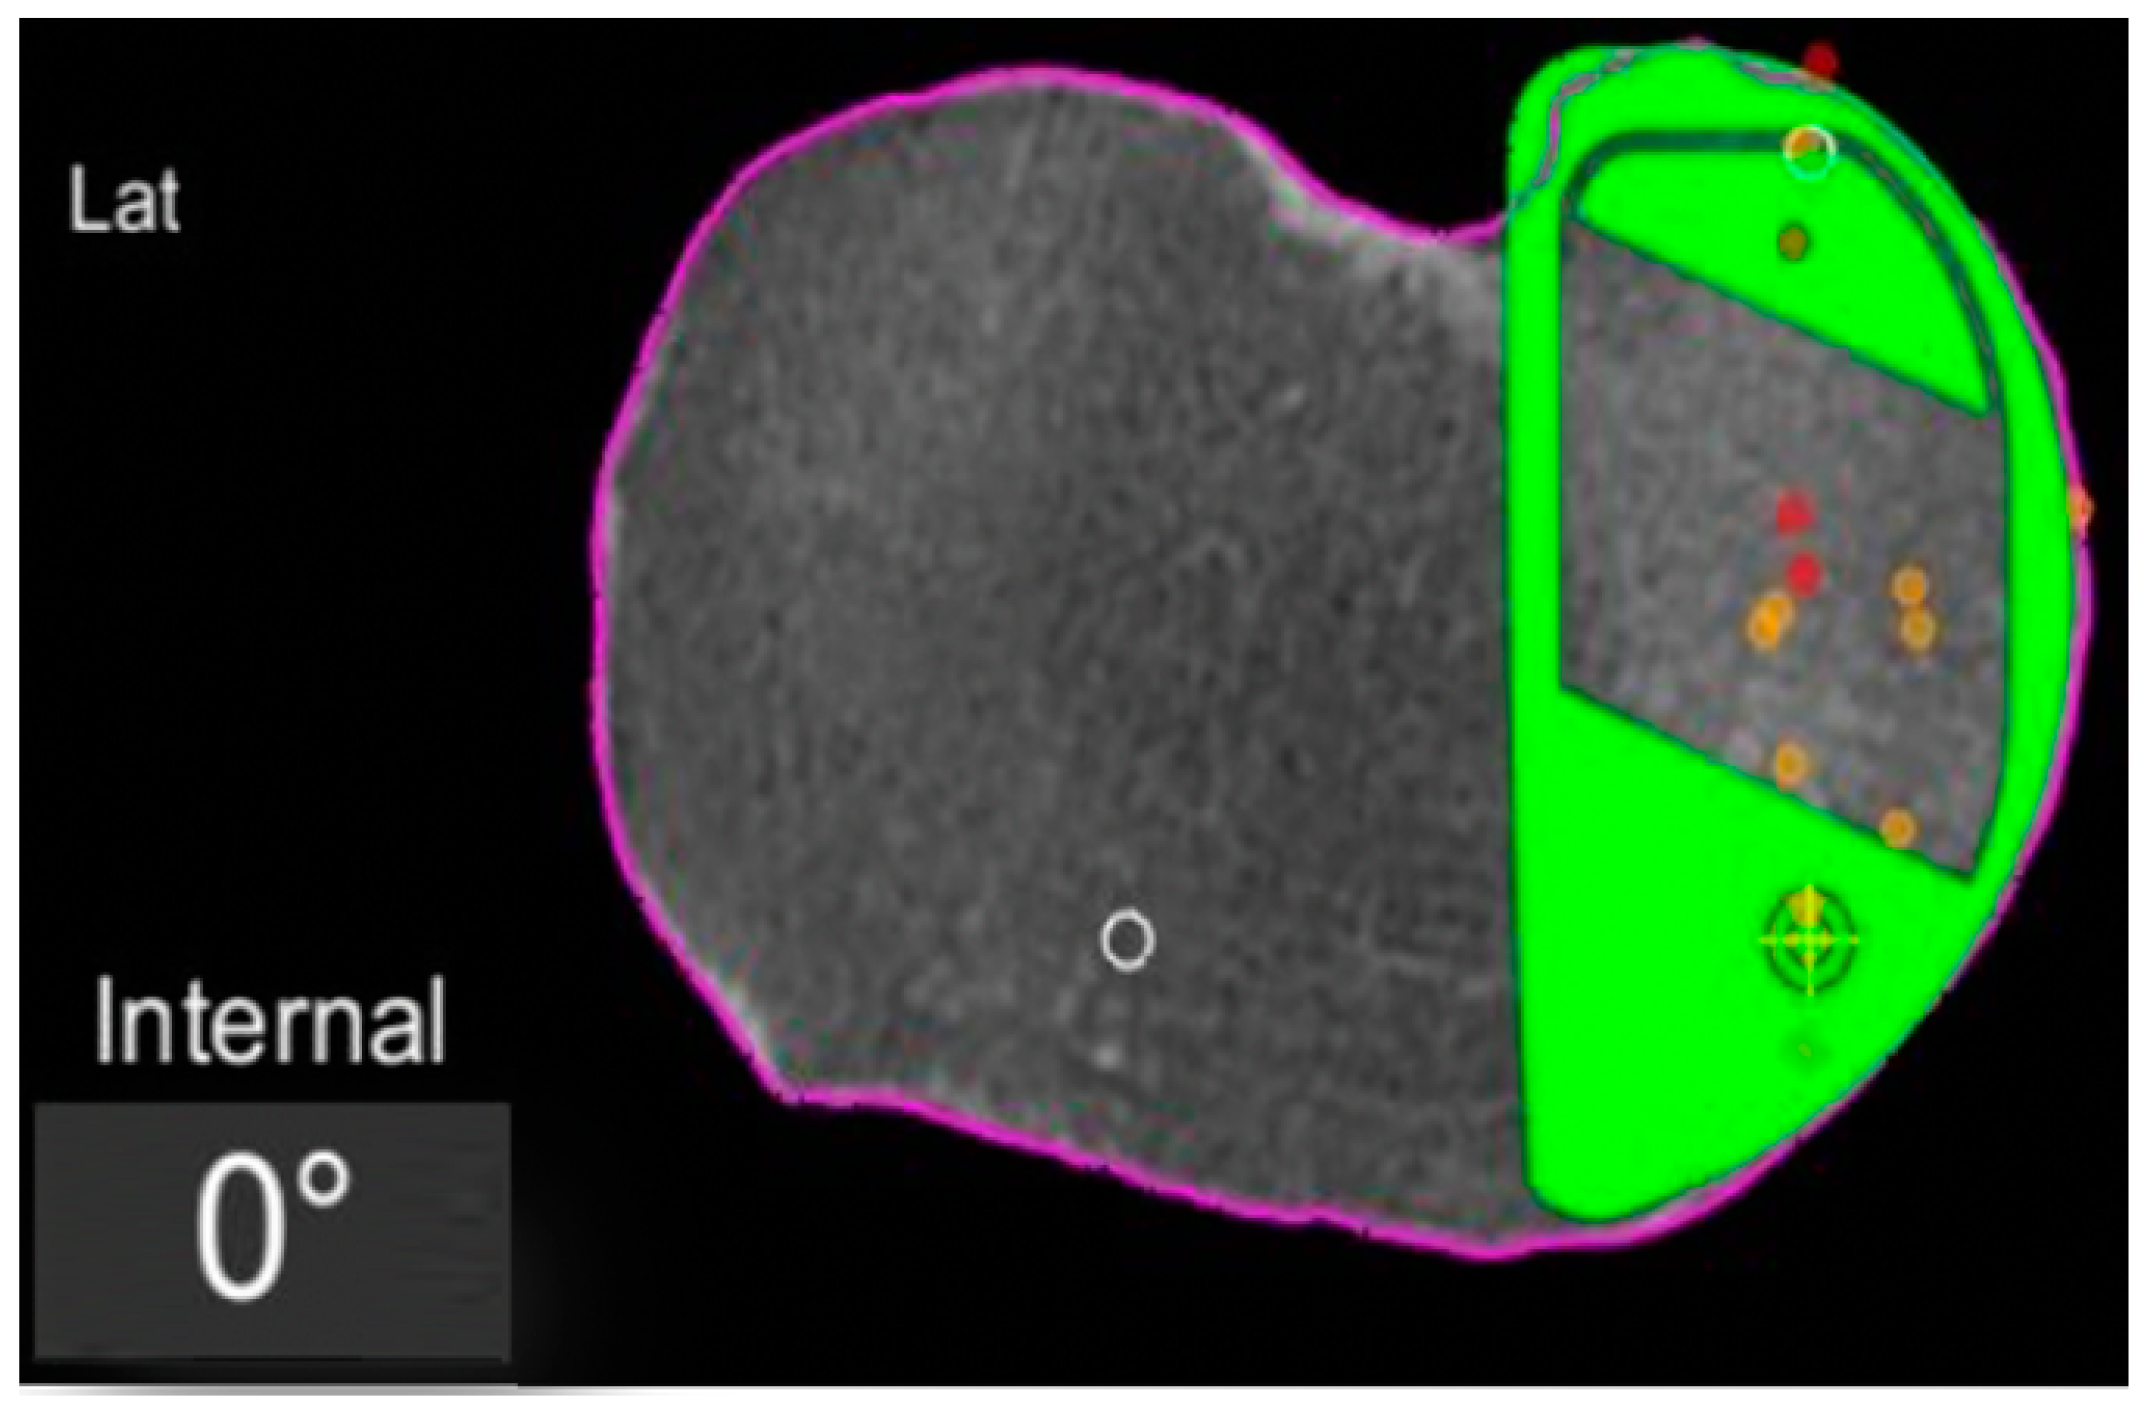

Figure 2.

Tibial component rotation (tibial rotation angle, TRA) is set to 0° considering the femur-based rotation landmark. The green area represents the implant. The purple line represents the segmentation of the CT-scan. Red dots are the recorded contact points of the femur on the tibia, yellow dots the cartilage level that was recorded with a blunt probe during surgery, in order to fine-tune the resection level.